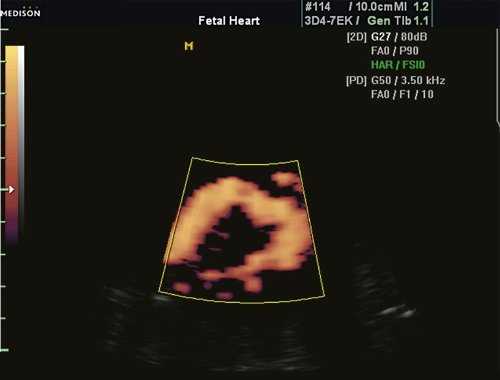

Но лидером в исследованиях гемодинамических процессов в сердце и сосудах плода считается доплер-эхокардиография.Этот метод оценивает три основных показателя -направление, скорость и характер кровотока. Процедура такова:на животе беременной устанавливается датчик УЗИ. На экран передается цветное изображение. Красным обозначается течение крови, которая двигается в сторону датчика.Синий цвет указывает на объем крови, идущий в обратном направлении. Максимальная интенсивность того или иного цвета обозначает повышенную гемодинамику.

При эхокардиографии изучались четырехкамерный срез сердца плода (рис. 1) и срез через три сосуда (рис. 2). УЗИ проводилось трансабдоминальным датчиком, лишь при необходимости (затрудненная визуализация) использовался внутриполостной датчик. Четырехкамерный срез сердца плода при ультразвуковом сканировании трансабдоминальным датчиком визуализировался в 85% случаев, срез через сосуды - в 73%, при использовании трансвагинального датчика эти цифры существенно возрастали до 100 и 91% соответственно. Оптимизация пренатальной диагностики ВПС может быть достигнута путем строгого соблюдения основных методических правил. При оценке четырехкамерного среза плода необходимо оценить нормальное расположение сердца плода, исключив его эктопию (рис. 3), положение оси сердца плода, что не представляет никаких трудностей, нормальные пропорции и размеры камер сердца, движение створок атриовентрикулярных клапанов должно быть свободным, септальная створка трикуспидального клапана должна располагаться ближе к верхушке сердца (рис. 4). При оценке среза через три сосуда необходимо оценить взаиморасположение сосудов и их диаметр.

Рис. 1. Беременность 12 недель. Четырехкамерный срез сердца плода. Отчетливо видны камеры сердца.